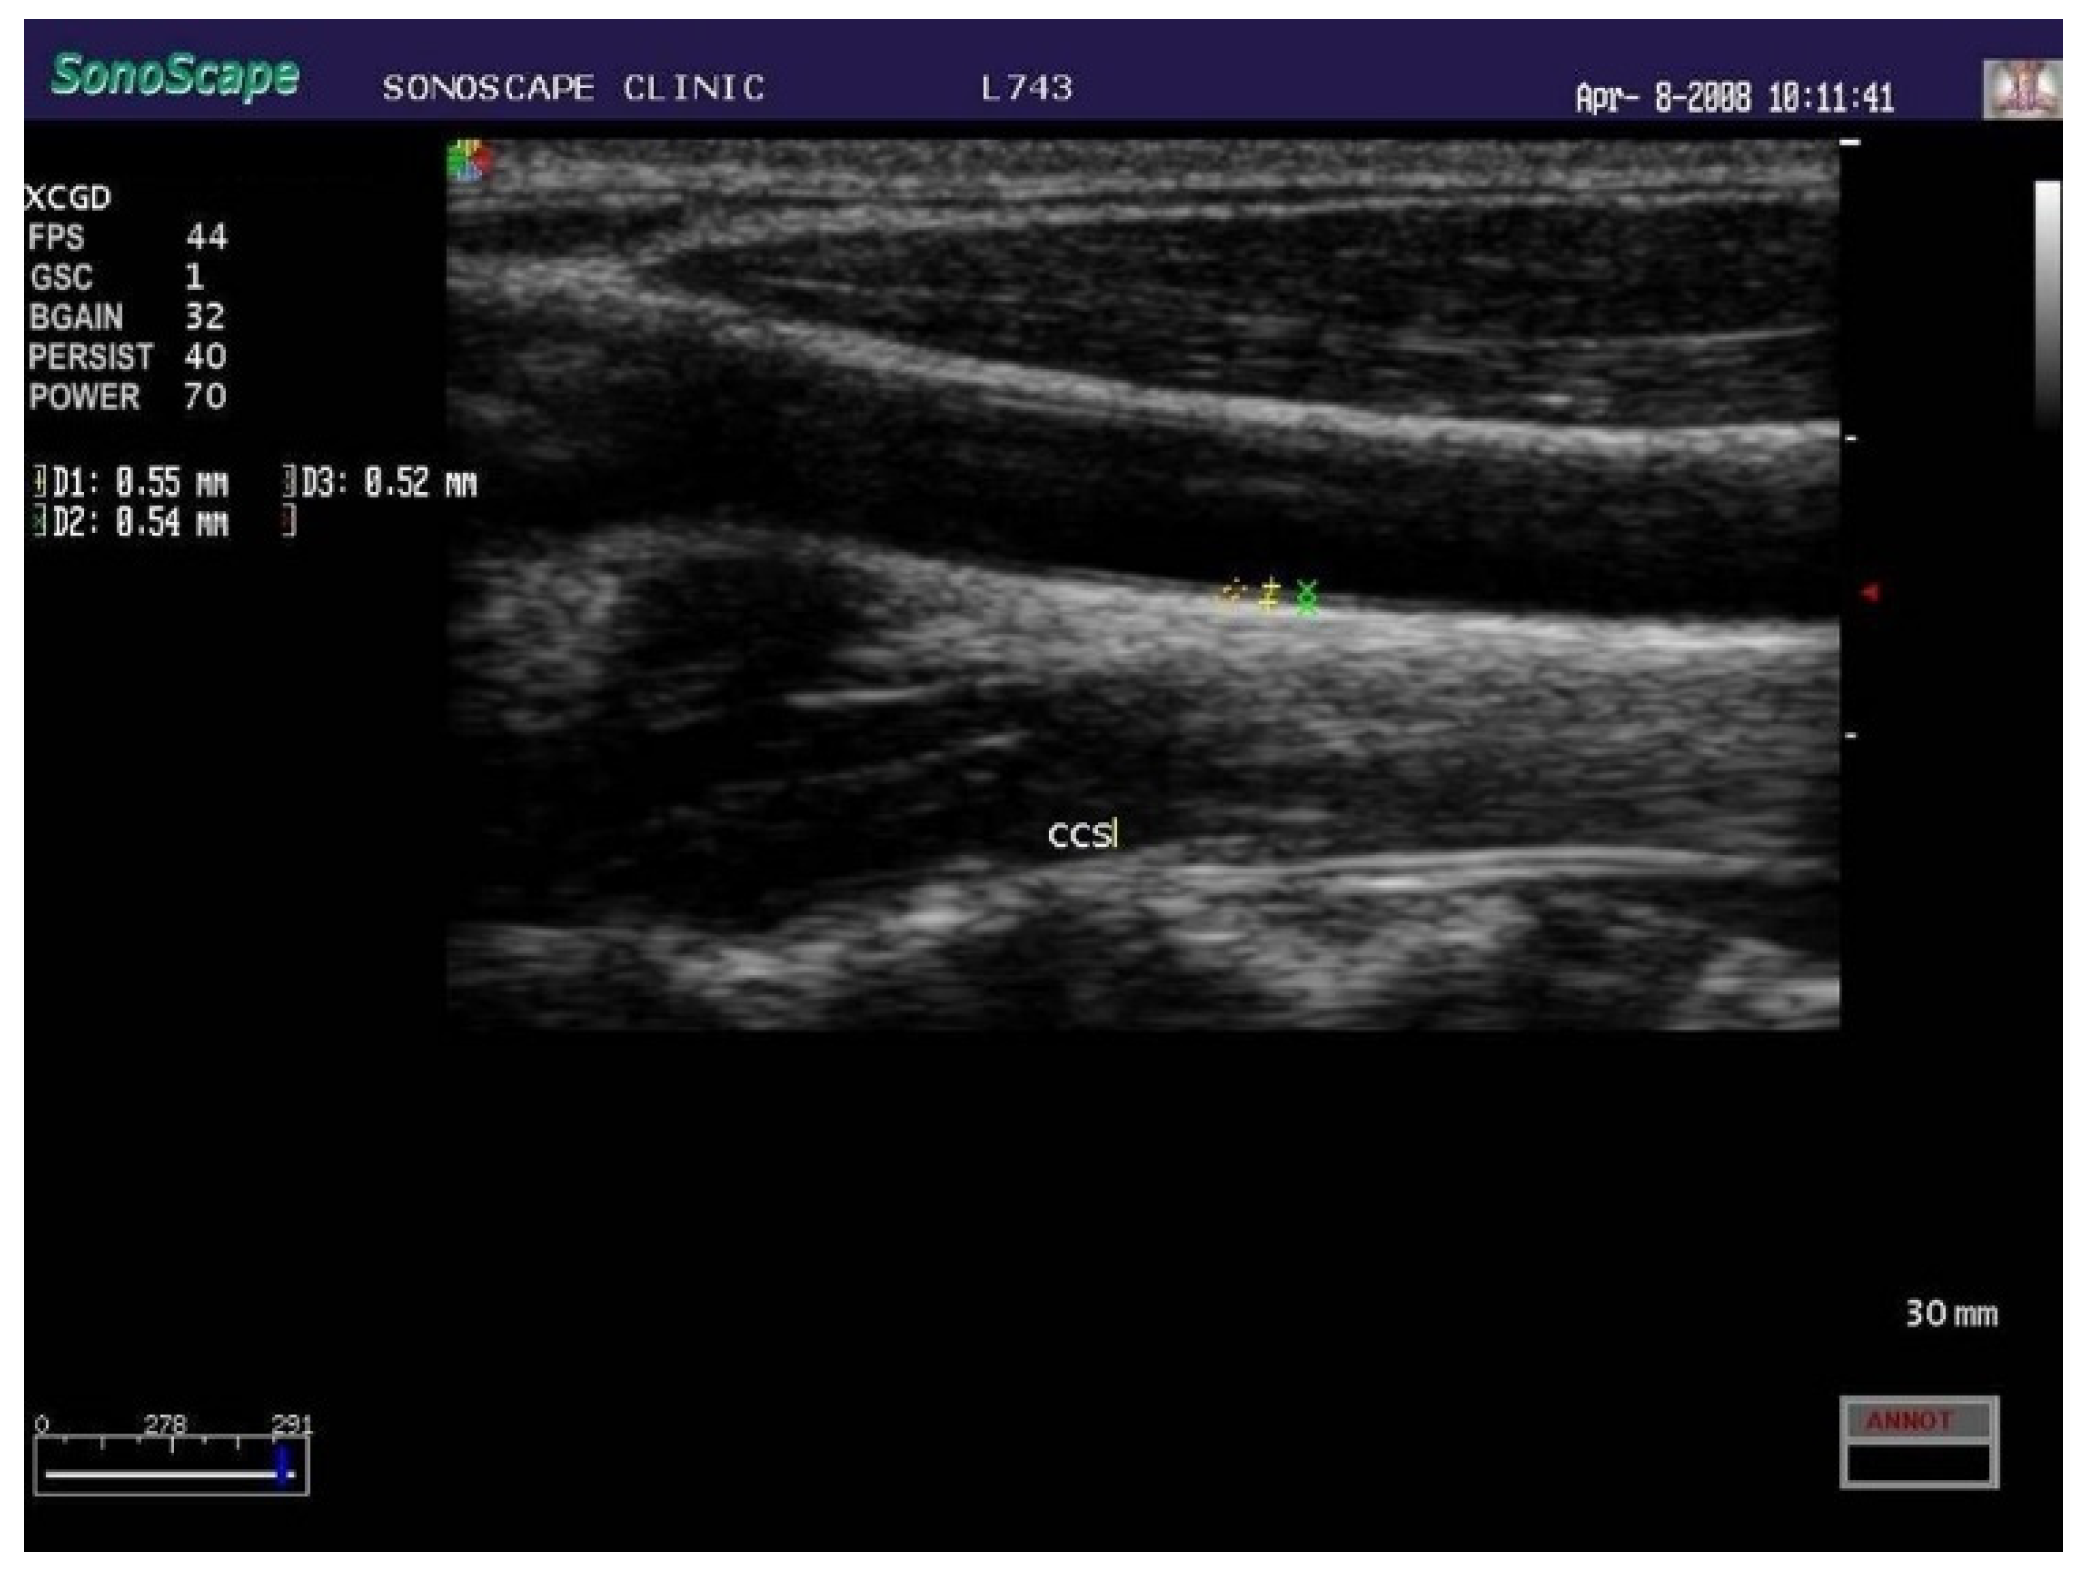

- Martino, F.; Loffredo, L.; Carnevale, R.; Sanguigni, V.; Martino, E.; Catasca, E.; Zanoni, C.; Pignatelli, P.; Violi, F. Oxidative stress is associated with arterial dysfunction and enhanced intima-media thickness in children with hypercholesterolemia: The potential role of nicotinamide-adenine dinucleotide phosphate oxidase. Pediatrics 2008, 122, e648–e655. [Google Scholar] [CrossRef]

- Loffredo, L.; Martino, F.; Carnevale, R.; Pignatelli, P.; Catasca, E.; Perri, L.; Calabrese, C.M.; Palumbo, M.M.; Baratta, F.; Del Ben, M.; et al. Obesity and hypercholesterolemia are associated with NOX2 generated oxidative stress and arterial dysfunction. J. Pediatr. 2012, 161, 1004–1009. [Google Scholar] [CrossRef]

- Masoura, C.; Pitsavos, C.; Aznaouridis, K.; Skoumas, I.; Vlachopoulos, C.; Stefanadis, C. Arterial endothelial function and wall thickness in familial hypercholesterolemia and familial combined hyperlipidemia and the effect of statins. A systematic review and meta-analysis. Atherosclerosis 2011, 214, 129–138. [Google Scholar] [CrossRef]

- Tonstad, S.; Joakimsen, O.; Stensland-Bugge, E.; Leren, T.P.; Ose, L.; Russell, D.; Bønaa, K.H. Risk factors related to carotid intima-media thickness and plaque in children with familial hypercholesterolemia and control subjects. Arterioscler. Thromb. Vasc. Biol. 1996, 16, 984–991. [Google Scholar] [CrossRef]

- Dalla Pozza, R.; Ehringer-Schetitska, D.; Fritsch, P.; Jokinen, E.; Petropoulos, A.; Oberhoffer, R.; Association for European Paediatric Cardiology Working Group Cardiovascular Prevention. Intima media thickness measurement in children: A statement from the Association for European Paediatric Cardiology (AEPC) Working Group on Cardiovascular Prevention endorsed by the Association for European Paediatric Cardiology. Atherosclerosis 2015, 238, 380–387. [Google Scholar] [CrossRef]